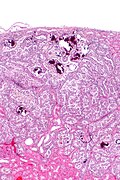

Papillary adenoma. H&E stain. | |

| LM | papillae typically with foam cells, +/-psammoma bodies, low ISUP nucleolar grade, must be <=1.5 cm |

- Histomorphology of papillary renal cell carcinoma with low ISUP nucleolar grade (grade 1 or 2).

- Must be <=1.5 cm as per 2016 WHO classification.[3]

- Diagnostic size cutoff - larger lesions are papillary renal cell carcinoma.